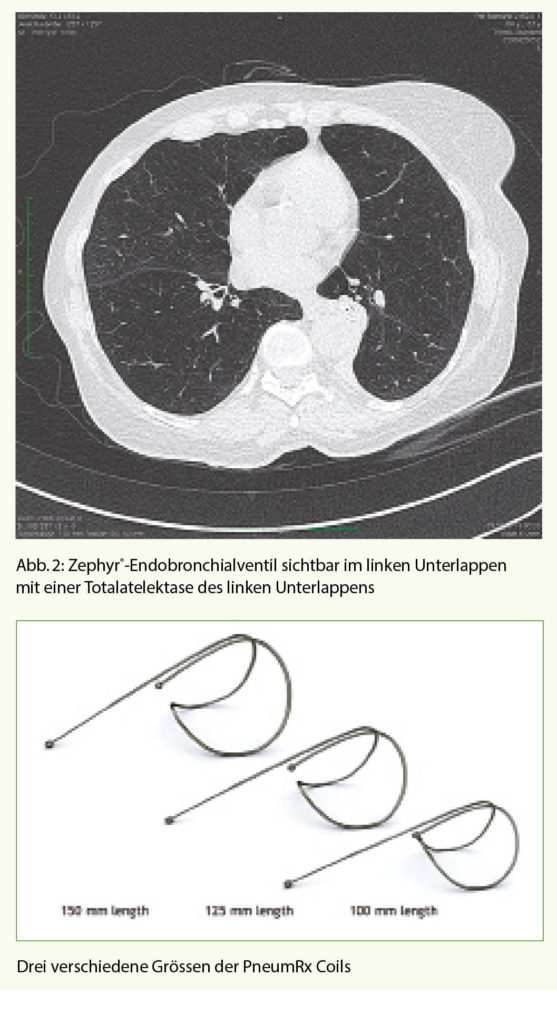

Das Ziel dieser Methode ist es, eine komplette Atelektase eines Lungenlappens zu erreichen und damit die Überblähung zu vermindern. Mittels Einlage von Einweg-Ventilen (Abb. 1) in den Segment- und Subsegmentbronchien in dem am meisten vom Emphysem betroffenen Lungenlappen wird ein unidirektionaler Luftfluss erzwungen. Das heisst, die Luft kann wohl während der Exspiration aus dem Lappen strömen, wird aber durch die Ventile bei der Inspiration blockiert, so dass es zu einer kontinuierlichen Entleerung des behandelten Lungenlappens kommt, im besten Fall zu einer Totalatelektase (Abb. 2).

Einen anderen Ansatz der Volumenreduktion verfolgt die Coil-Therapie. Diese Coils (Abb. 3) entfalten ihre Wirkung durch Raffung des Lungengewebes über Zug an den Atemwegen.

Bei den Coils handelt es sich um Drähte aus Nitinol, welche in gestrecktem Zustand über das flexible Bronchoskop in die Atemwege eingelegt werden und dort nach der Implantation ihre Spiralform wieder annehmen. Neben dem volumenvermindernden Effekt kommt es zu einer zusätzlichen Traktion an den Atemwegen (Zunahme des elastic recoil), welche durch die Coils offen gehalten werden. Insbesondere unter Belastung scheint sich diese Wirkung zu entfalten (Abnahme der dynamischen Überblähung). Es werden bis zu 12 Coils in einem Lungenlappen subsegmental implantiert. Das Vorgehen wird dann idealerweise auf der kontralateralen Seite nach 1 Monat wiederholt (Abb. 4).

Dieses Verfahren kann sowohl bei vorhandener Kollateralventilation wie auch beim homogenen Emphysemtyp angewandt werden, ist aber irreversibel. Die Nebenwirkungen sind ähnlicher Art wie bei der Ventileinlage, wobei die Pneumothoraxrate deutlich geringer ist mit etwa 6%. In den ersten 30 Tagen kann es zu Thoraxschmerzen und Hämoptysen führen, welche aber im weiteren Verlauf meist spontan verschwinden. Auch dieses Verfahren kann sowohl in Narkose wie auch beim lediglich sedierten Patienten erfolgen und bedarf einer mehrtägigen Hospitalisation. Eine Meta-Analyse von 5 Studien mit total 125 Patienten zeigte nach 6 Monaten eine signifikante Verbesserung im 6-Minuten-Gehtest von 44 Metern und einen Anstieg des FEV1 um 80ml. Eindrücklicher war die klinische Verbesserung mit einer Abnahme im SGRQ-score von 9.5 Punkten. Auch nach 12 Monaten waren diese Resultate noch signifikant vorhanden (12).